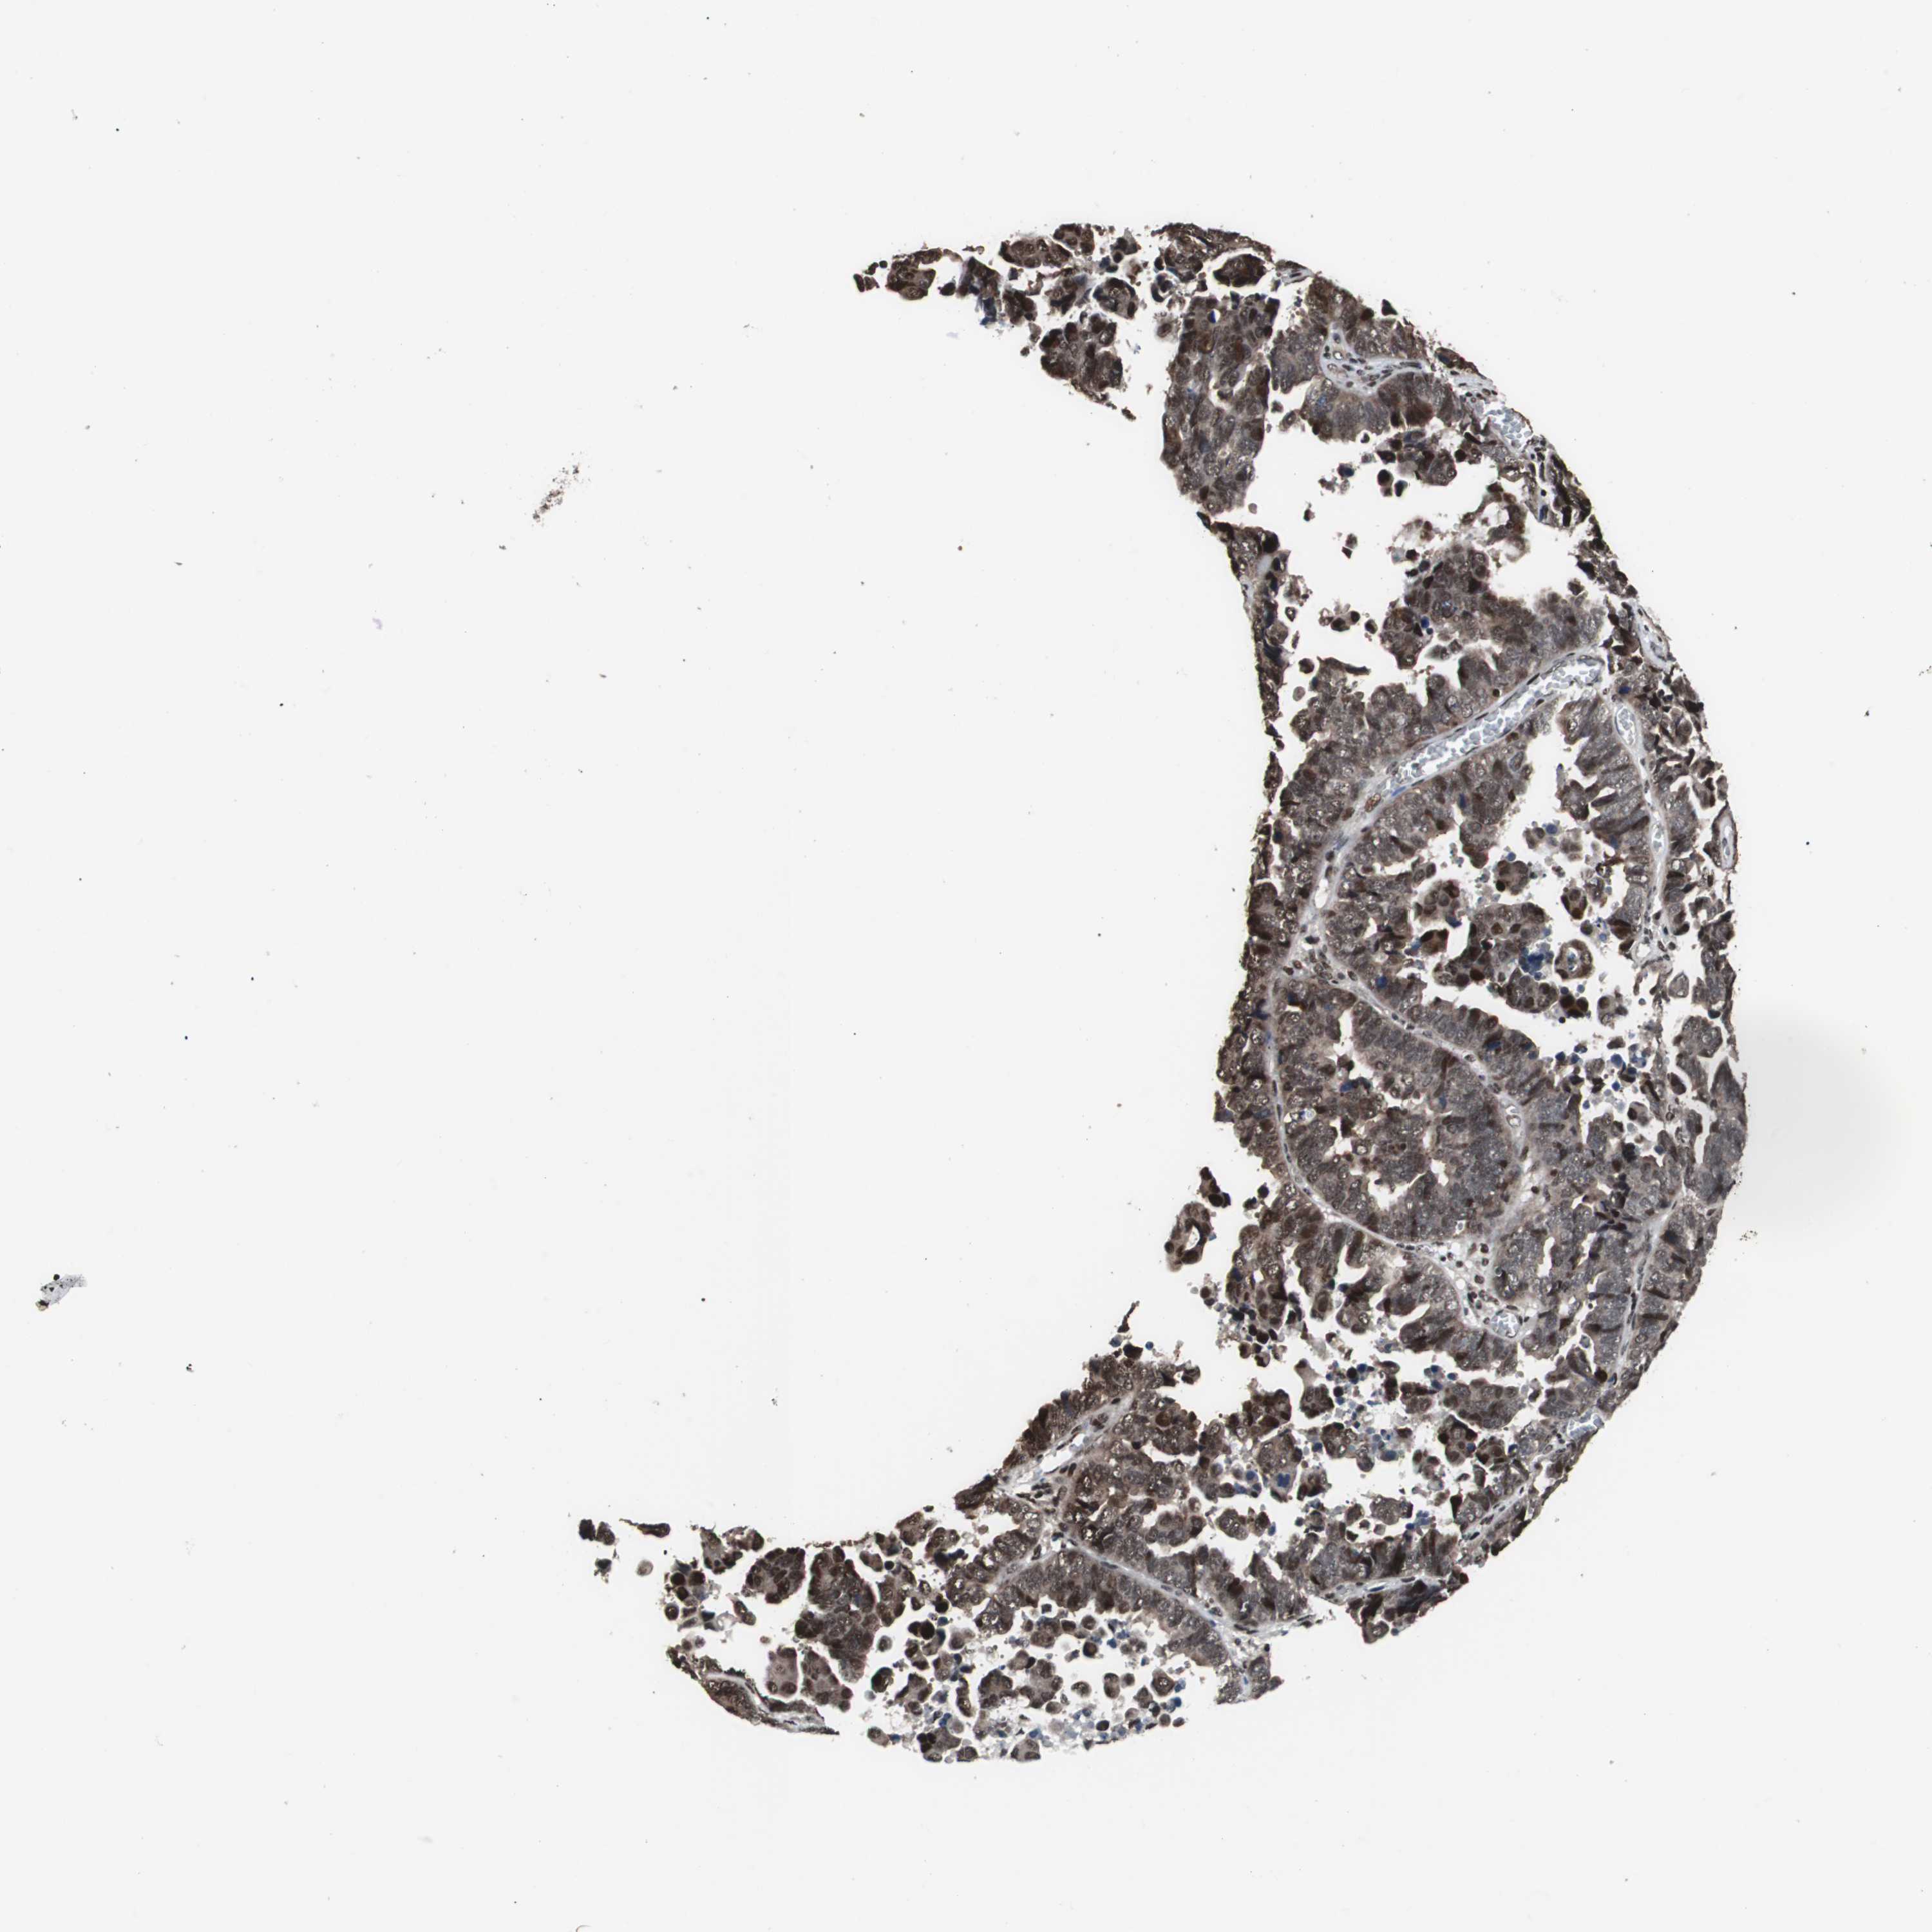

ENDOMETRIAL CANCER - Protein expressioni

A mouse-over function shows sample information and annotation data. Click on an image to view it in a full screen mode. Samples can be filtered based on level of antibody staining by selecting one or several of the following categories: high, medium, low and not detected. The assay and annotation is described here.

Note that samples used for immunohistochemistry by the Human Protein Atlas do not correspond to samples in the TCGA dataset.

Antibody stainingi

Antibody staining in the annotated cell types in the current human tissue is reported as not detected, low, medium, or high, based on conventional immunohistochemistry profiling in selected tissues. This score is based on the combination of the staining intensity and fraction of stained cells.

Each image is clickable and will lead to virtual microscopy that enables deeper exploration of all samples and also displays staining intensity scores, fraction scores and subcellular localization as well as patient and tissue information for each sample.

Antibody HPA006982

Staining

High

Medium

Low

Not detected

Intensity

Strong

Moderate

Weak

Negative

Quantity

>75%

75%-25%

<25%

None

Location

Nuclear

Cytoplasmic/membranous

Cytoplasmic/membranous,nuclear

Adenocarcinoma, NOS